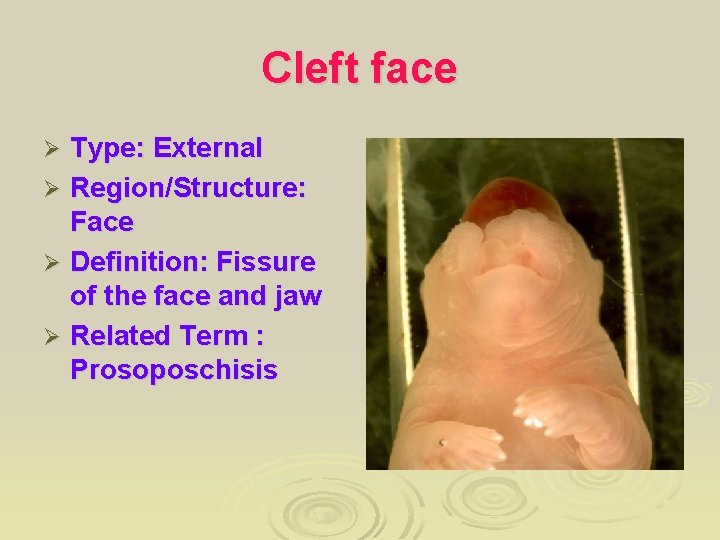

Cleft face Type: External Ø Region/Structure: Face Ø Definition: Fissure of the face and jaw Ø Related Term : Prosoposchisis Ø